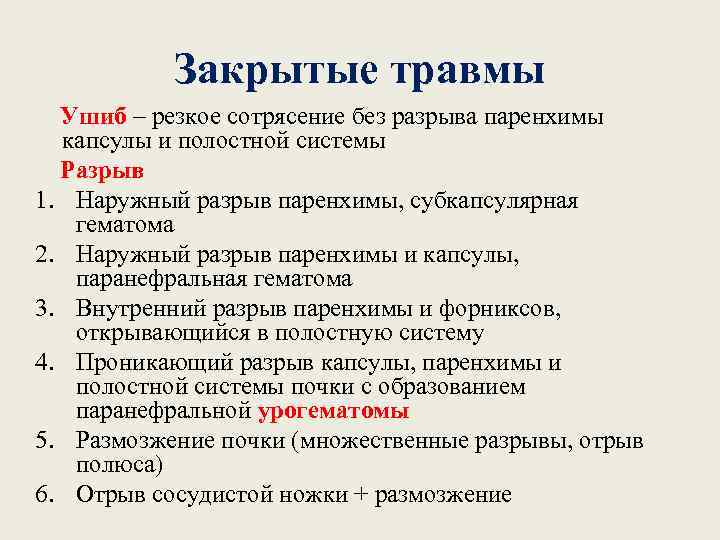

Закрытые травмы Ушиб – резкое сотрясение без разрыва паренхимы капсулы и полостной системы Разрыв 1. Наружный разрыв паренхимы, субкапсулярная гематома 2. Наружный разрыв паренхимы и капсулы, паранефральная гематома 3. Внутренний разрыв паренхимы и форниксов, открывающийся в полостную систему 4. Проникающий разрыв капсулы, паренхимы и полостной системы почки с образованием паранефральной урогематомы 5. Размозжение почки (множественные разрывы, отрыв полюса) 6. Отрыв сосудистой ножки + размозжение